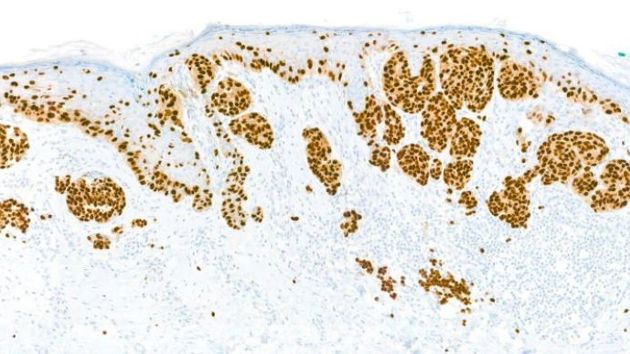

Enthousiaste sprekers geven op deze dag uitleg over IF en immuunkleuringen in de diagnostiek van huidafwijkingen. In het kader van de IVDR wetgeving leggen een spreker van de NVVP en een gespecialiseerde analist uit wat de IVDR voor onze kleuringen betekent. De dag is bedoeld voor iedereen die immuunkleuringen doet en alle andere geïnteresseerden.